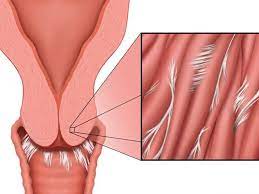

قیمت: 45٬000 تومان - دسته بندی فایل: پاورپوینتدانلود پاورپوینت آشرمن یا چسبندگی رحمی و درمان آن

خرید پاورپوینت حرفه ای با موضوع آشرمن یا چسبندگی رحمی و درمان آن با قیمت استثنایی از لوکس فایل